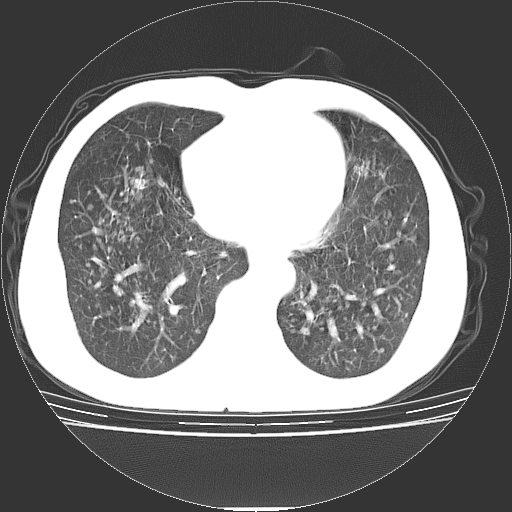

以下是引用yangyudong333在2008-4-29 5:38:00的发言:[br]比较典型的矽肺结节.支持[br]诊断依据:[br] 1.x线表现:[br] ①典型矽肺为多发直径 1~3mm 小结节,即矽结节,由胶原纤维和硅尘构成,可融合成团块,好发于上肺。[br] ②团块周围常有肺大泡。[br] ③胸内淋巴结增大、钙化。如肺门淋巴结呈蛋壳样钙化有助于与其他尘肺区别。[br] ④胸膜常广泛粘连、增厚。[br] 2.ct表现[br] ①两肺散在大小较为一致的小结节影,其密度较高,边界清楚。[br] ②小结节可融合为较大团块影,直径约 1cm ,甚至可达 10cm以上,易发生在上叶。[br] ③小结节周围常并有小叶中心气肿或弥漫性肺气肿。

以下是引用liuyue在2008-4-28 22:30:00的发言:[br]比较典型的矽肺结节.[br]请结合临床及化验除外矽肺合并肺结核之可能.